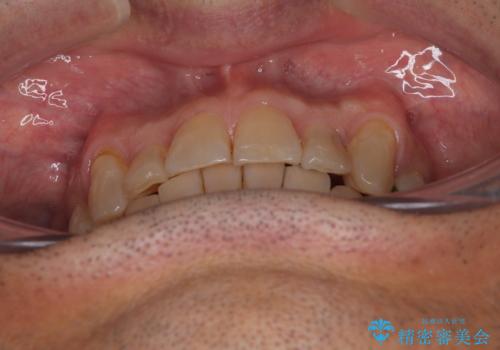

奥歯の欠損と前歯のデコボコを治したい インプラントと矯正治療の総合歯科治療

銀歯やむし歯治療されている歯を抜歯する治療計画としたため、やや時間はかかりましたが、治療後の仕上がりには大変満足していただけました。